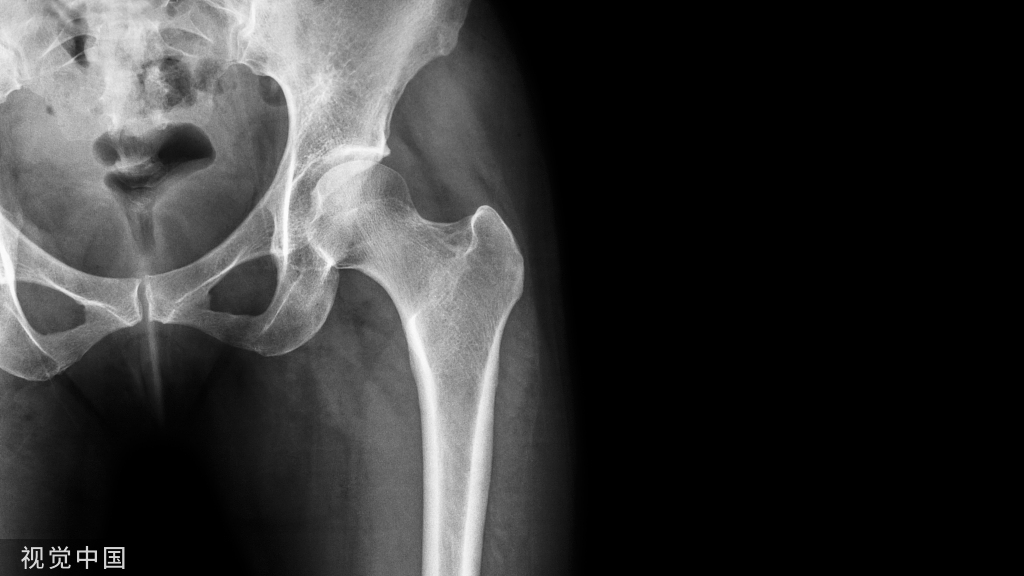

X 线平片上表现为伴有清晰薄层硬化缘的环形(囊状)透亮区,CT 上表现为圆形 或类圆形的皮质下局灶性骨质缺损,周围见薄层硬化带环绕,边缘锐利,部分较大病灶在病灶层面或上下相邻、层面上前方显示皮质与病灶相通的局部裂隙样缺损病灶,最大径线通常小于 10 mm;MRI 示病灶在 T1WI 上呈低信号,在 T2WI 上呈均匀或不均匀高信号。